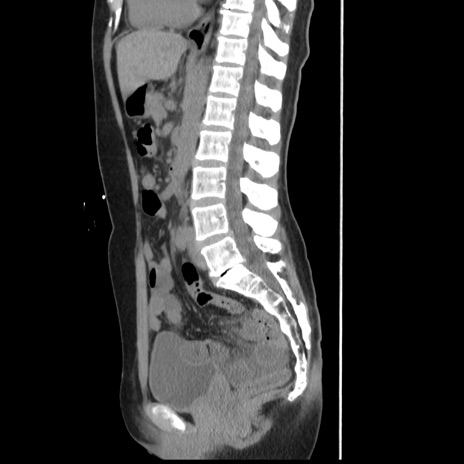

症例10(矢状断像)

【症例】 50歳代女性

【主訴】 腹痛

【現病歴】前日生レバーを食べた。今朝に排便あり。 昼前に突然発症の腹痛を生じ、当院救急外来を受診した。

【既往歴】 子宮筋腫にてで子宮全摘後

【身体所見】 意識清明、腹部:平坦、軟、下腹部やや左を中心に圧痛・反跳痛あり、筋性防御あり

【データ】WBC 7800、CRP 0.07